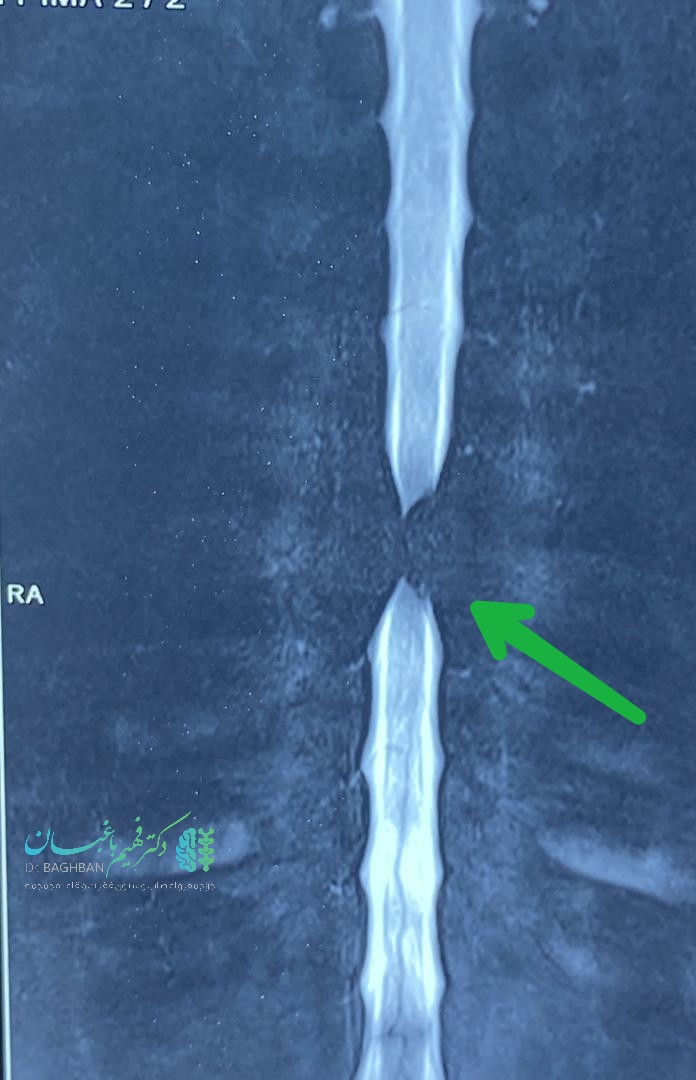

آقای میانسال با ضعف پیشرونده اندام های تحتانی و بی اختیاری ادرار و مدفوع مراجعه کرده بودند. تومور همانژیومای مهاجم مهره ششم توراسیک که سبب آسیب نخاع شده بود. بیمار با نورومانیترینگ دائمی تحت عمل جراحی قرار گرفتند که ابتدا نخاع آزاد و سپس کل مهره توسط سیمان ،ورتبروپلاستی شد. با تشکر از آقای دکتر حسین زاده، همکار محترم جراح اعصاب که عمل با یاری ایشان صورت گرفت.

تصاویر قبل و بعد ازعمل